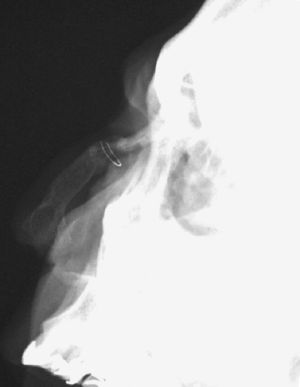

Se reinterrogó al paciente que relató que en una de las intervenciones previas, y para reconstruir la anatomía nasal, se realizó un injerto con hueso propio de la cadera. Realizamos un estudio radiográfico que evidenció la presencia de otro alambre de sutura que servía para fijar una estructura ósea anómala que correspondía al injerto de cadera utilizado para la reconstrucción nasal (fig. 2).